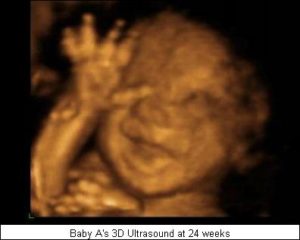

3Д ― трехмерное сканирование. Позволяет получить статичное, но объемное и наиболее информативное изображение плода. В ходе скрининга можно рассмотреть черты лица и мимику ребенка. 3D-УЗИ проводят на 20―28 неделе беременности.

4Д ― четырехмерное сканирование. Врач фиксирует трехмерное видеоизображение плода в текущий момент. После диагностики родители получают диск с небольшим «фильмом», который позволяет увидеть черты лица, мимику и движения малыша.

Кроме того, сочетание двухмерного и трёхмерного УЗИ плода является уникальным диагностическим методом, который даёт возможность увидеть ребёнка максимально реалистично, таким, каким он является, вплоть до пальчиков на руках и ногах.